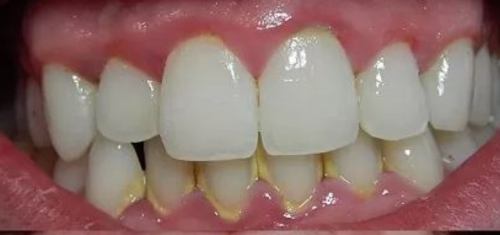

Before And After Dental Treatment

Before / After

From stained or misaligned teeth to a radiant, confident smile, our results speak for themselves. See the difference professional dental treatment can make — and imagine what we can do for you.

Teeth Cleaning (Scaling & Polishing)